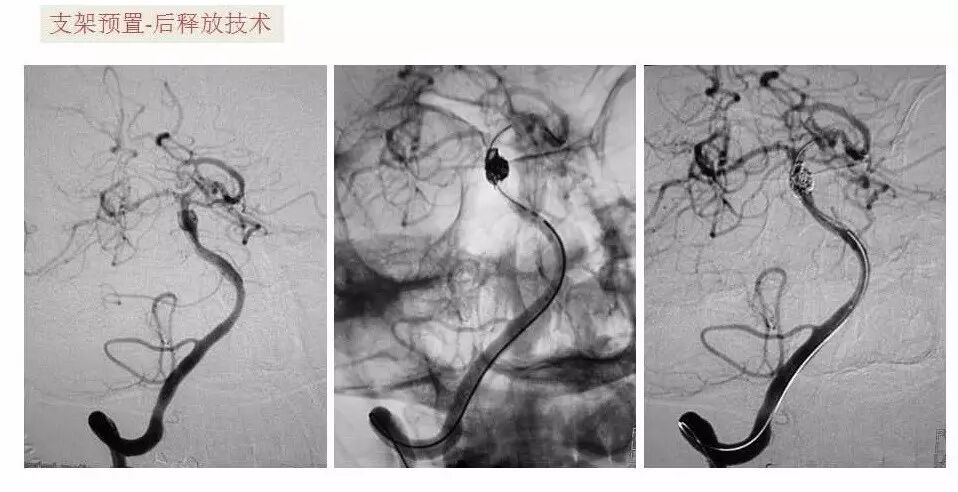

今天为大家分享的是“强生医疗CNV-神经介入专栏”第十五期,由首都医科大学宣武医院何川教授带来的“颅内动脉瘤介入治疗”精彩讲课视频及PPT,欢迎观看、阅读。文章仅代表作者个人观点,如有不同见解,欢迎同道斧正!